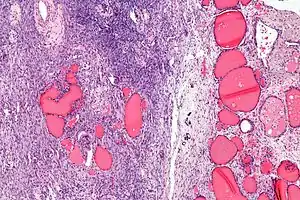

| Micrograph of a struma ovarii. Characteristic thyroid follicles are seen on the right, and ovarian stroma on the left. H&E stain. | |

A struma ovarii (literally: goitre of the ovary) is a rare form of monodermal teratoma that contains mostly thyroid tissue, which may cause hyperthyroidism.[1]